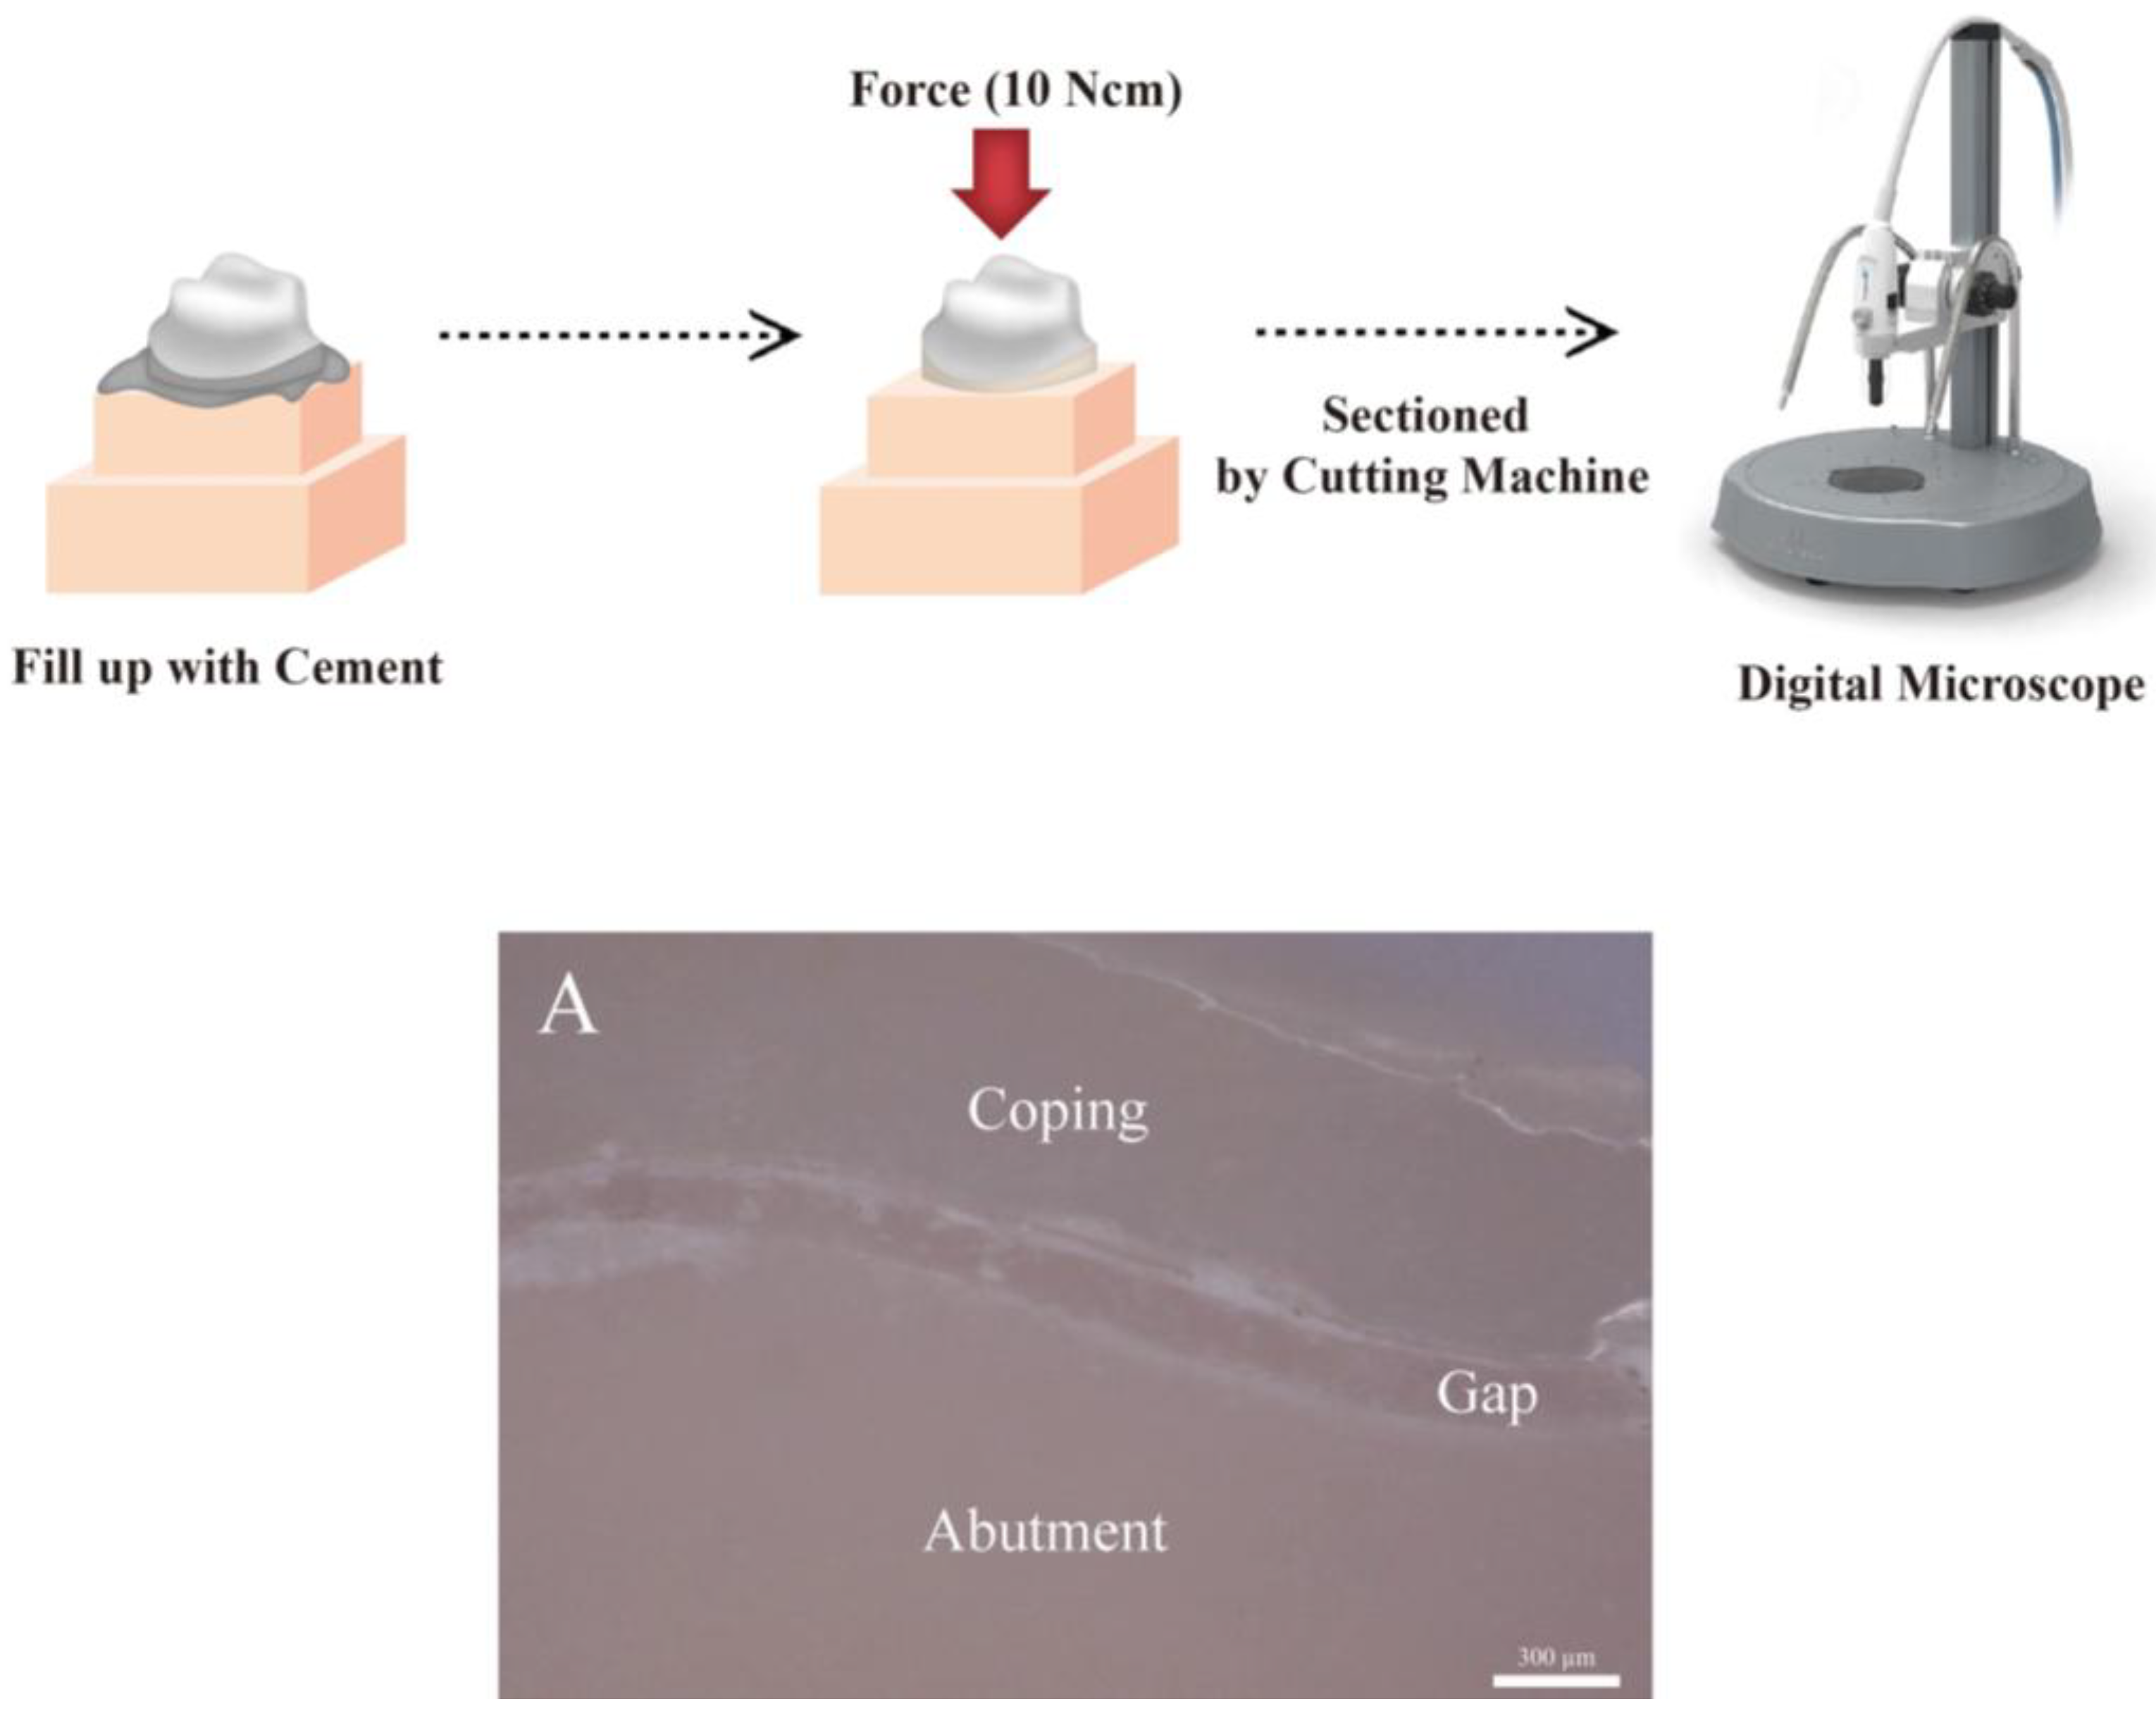

- The triple scan method (TSM): the TSM is a method of scanning the internal and external aspects of the prosthesis, the abutment tooth, and the prosthesis at the try-in stage in order to obtain three-dimensional (3D) data and measure the marginal and internal fit by overlapping the 3D data on an analysis software. It is a non-destructive, non-radioactive method capable of providing reproducible results at any time by scanning the data. However, miscalculations may occur due to possible inaccuracy and overlapping of the scanned data [27,28,34,35].

2.2.3. Triple Scan Method (TSM Group)